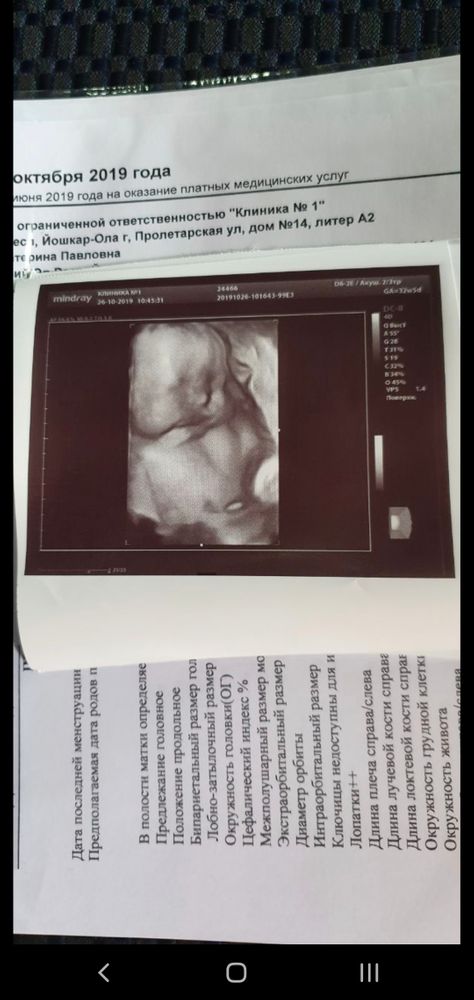

Ходила на внеплановое узи, т.к на 3м скрининге было 1.5 кратное обвитие. Очень переживала, хотя узист успокоил, сказал, что для малыша не опасно. И как итог, на сроке 35+5 обвития нет) И, конечно, дали фоточку, уже последнюю, теперь только ждёт наша встреча с малышом🥰 ПКС в 38 недель. Первое фото, это младший сын, на втором, старший. Оба щекастые на фото, хотя в жизни обычные щечки☺️ Разница в возрасте, получается, в 2.9мес